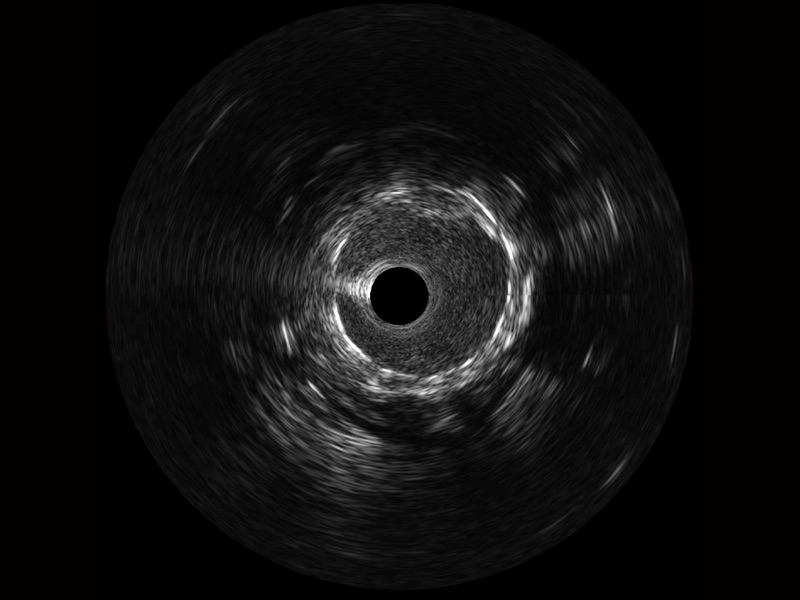

传统IVUS图像

对比传统IVUS导管成像,新葡的京集团8814检测站宽频IVUS图像的近场支架梁显影更细腻,远场中膜外血管仍清晰可辨,兼顾远中近,兼顾分辨力与穿透深度